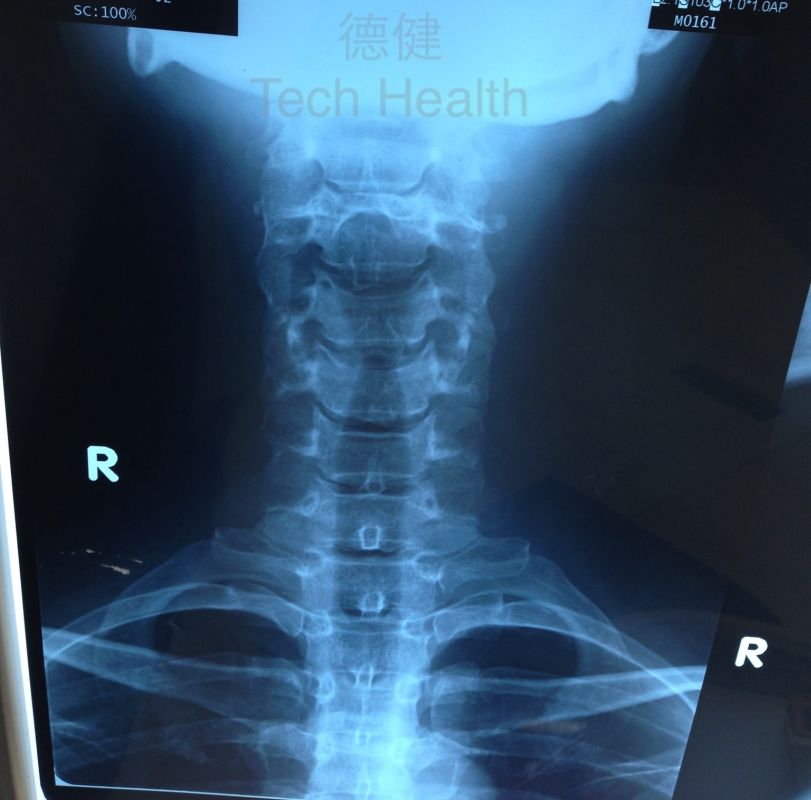

個案六 - 譚女士 45歲 - 從X光片檢查發現患者頸椎生理弧度異常,並患有退行性頸椎病。

2.從X光片檢查發現患者頸椎生理弧度異常,並患有退行性頸椎病。